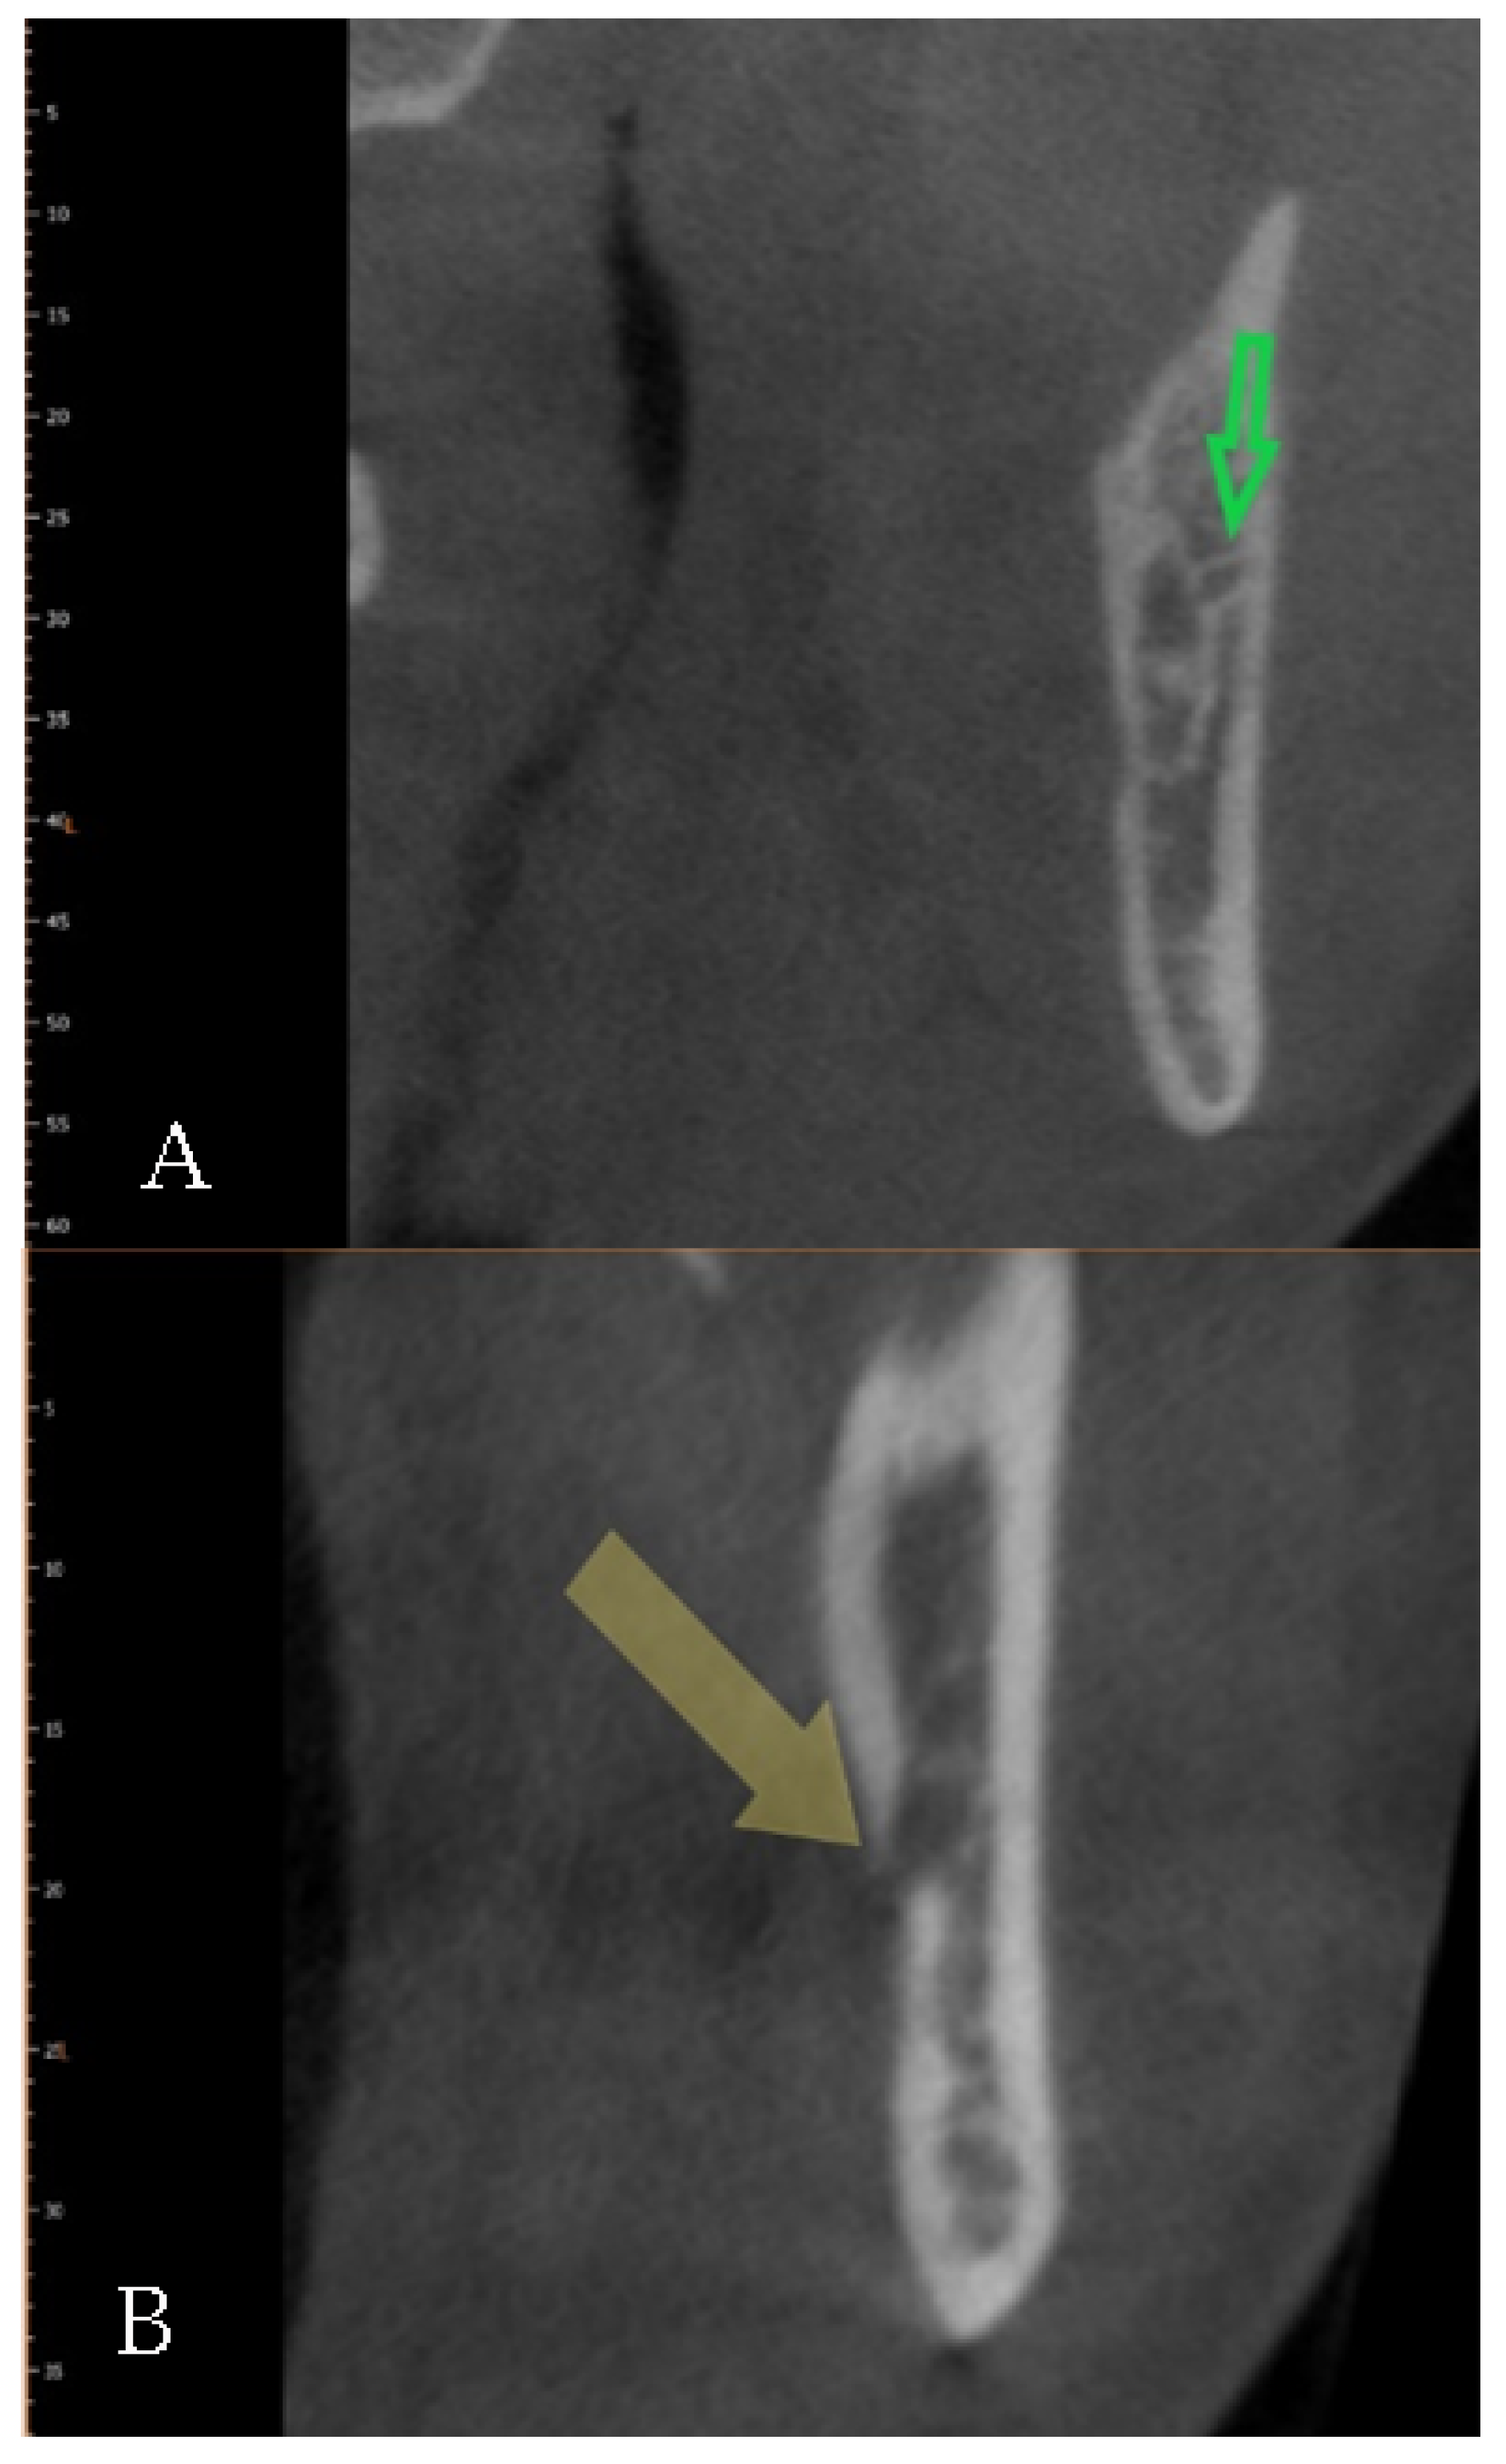

| Type 3 Front | 23.3 | 11.7 | 27 (9) | 16 (5.3) | 43 (14.3) | 11 (3.7) | 16 (5.3) | 27 (9) |

| Confluent | 12 | 6 | 16 (5.3) | 9 (3) | 25 (8.3) | 3 (1) | 8 (2.7) | 11 (3.7) |

| Not confluent | 11.3 | 5.7 | 11 (3.7) | 7 (2.3) | 18 (6) | 8 (2.7) | 8 (2.67) | 16 (5.3) |